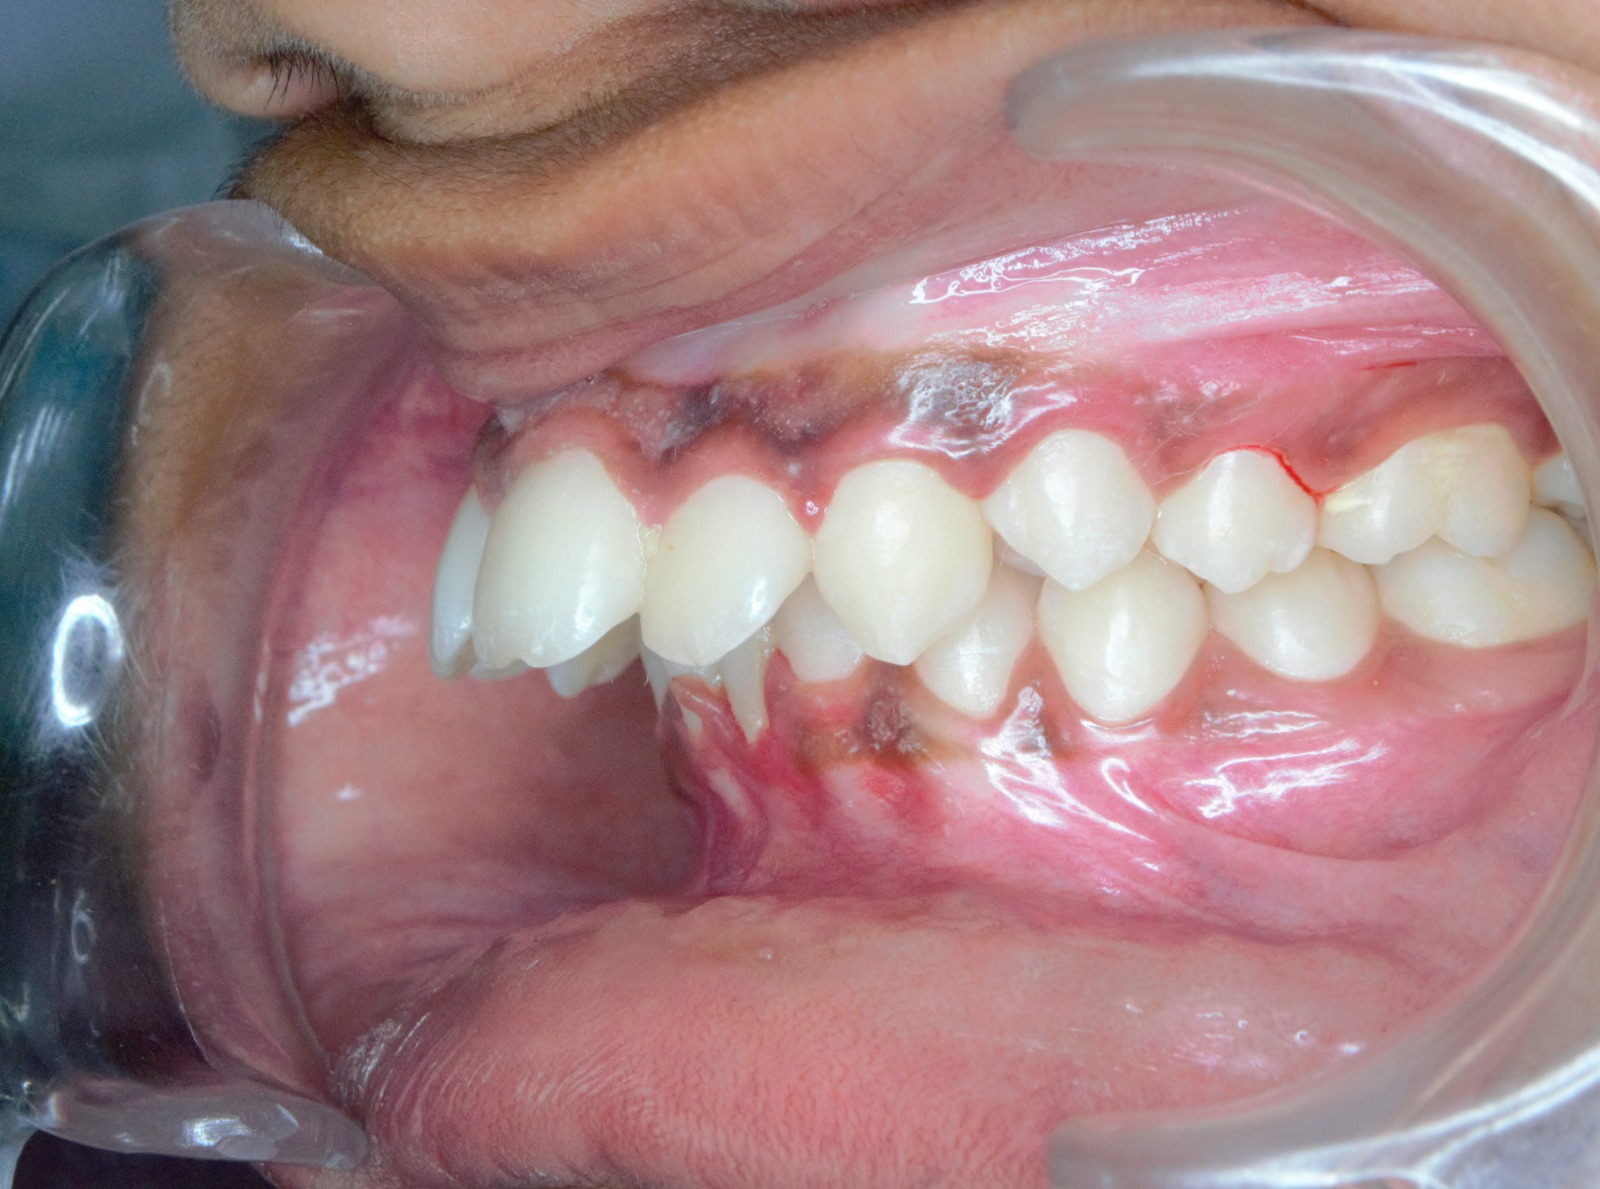

After/Before

See stunning smile transformation before and after